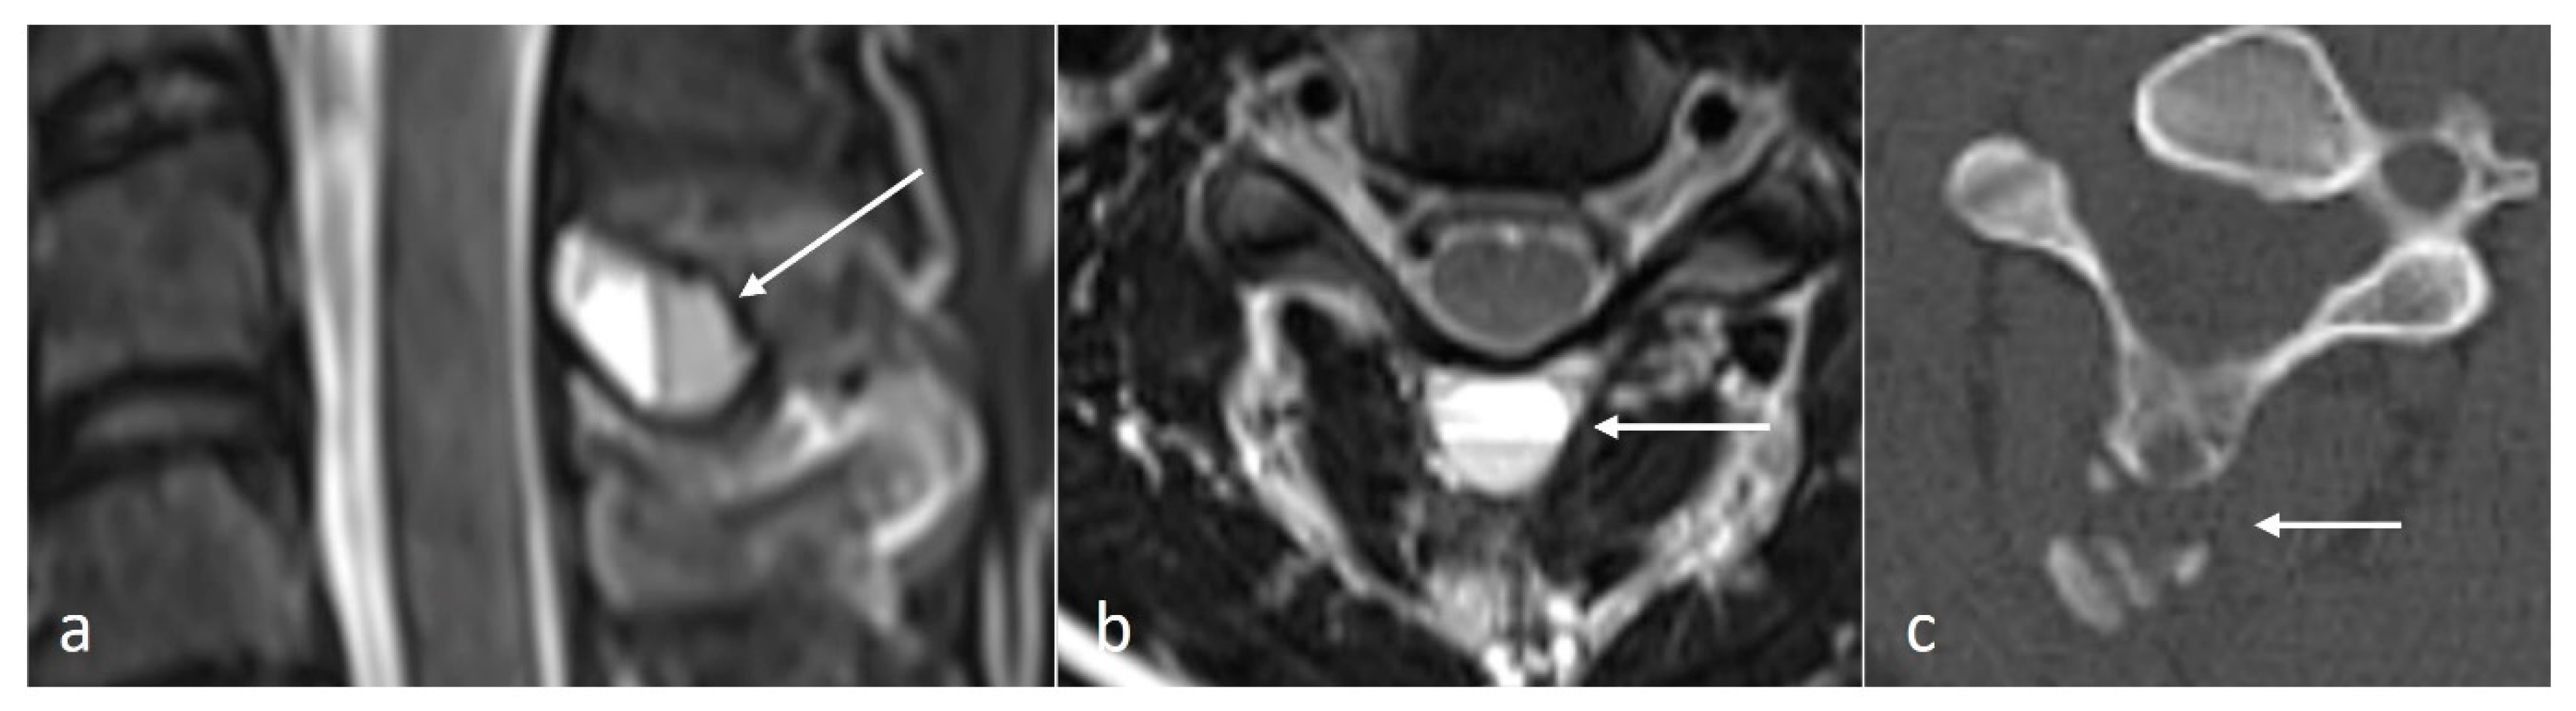

3.3.4. Aneurysmal Bone Cyst (ABC)

ABCs are benign locally aggressive lesions, with a predilection for the posterior spinal elements [15,18]. The lesions tend to be lytic and expansile. Thin bony septa may be present within the lesion, best appreciated on CT. MRI will show a cystic lesion with high signal on fluid-sensitive sequences, and the typical fluid–fluid levels. (Figure 4a–c) Rarely, solid components may also be present. These components as well as the septa can enhance.

Figure 4.

Sagittal T2 (a), axial T2 (b) and axial CT (c) images demonstrating an aneurysmal bone cyst of a cervical spinous process (white arrows). Note the lytic osseous destruction on CT and the characteristic presence of fluid–fluid levels on MRI.

It is important to distinguish primary ABCs from secondary ABC change occurring in association with other lesions such as fibrous dysplasia, GCT and even osteosarcoma, and the rare telangiectatic osteosarcoma, although osteosarcomas isolated to the spinous process are rare [3].